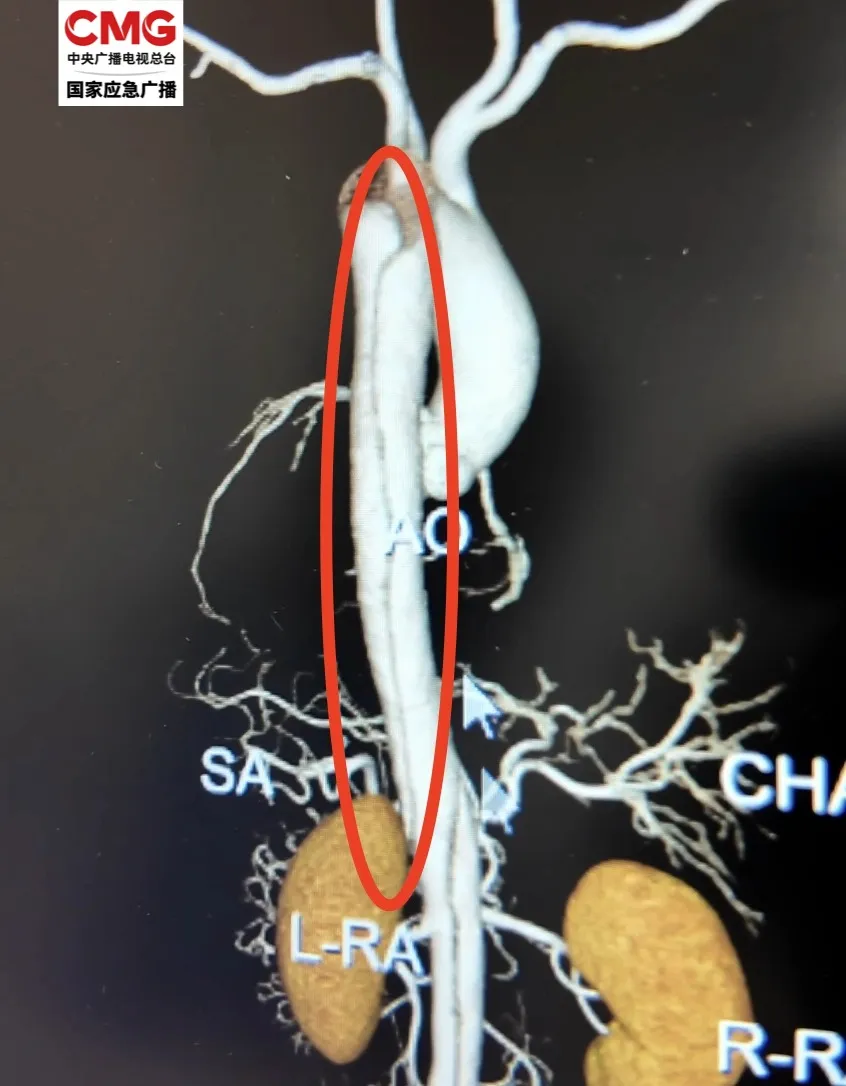

图中红圈处发生主动脉夹层